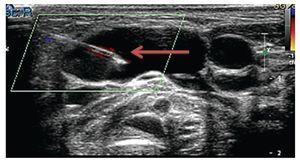

Laboratory studies, blood count, blood chemistry, blood gases and karyotype were normal. Computed axial tomography of the lateral neck showed clear asymmetry in volume with a left predominance at the expense of a hypodense, ill-defined image with apparent liquid attenuation. Vascular structures were shifted medially and later, anterior to the sternocleidomastoid muscle. In this image we observed parapharyngeal fat displacing the air space to the right. Compression and conditioning gauge decreased >50% (Fig. 2).

Figure 2 Computed axial tomography of the head and neck. Increased volume of the neck is observed predominantly on the left that displaces medial and posterior (arrows) vessels, anterior to the sternocleidomastoid muscle, with linear vascular hyperdense images in the interior. Reinforcement is not identified after administration of contrast medium.